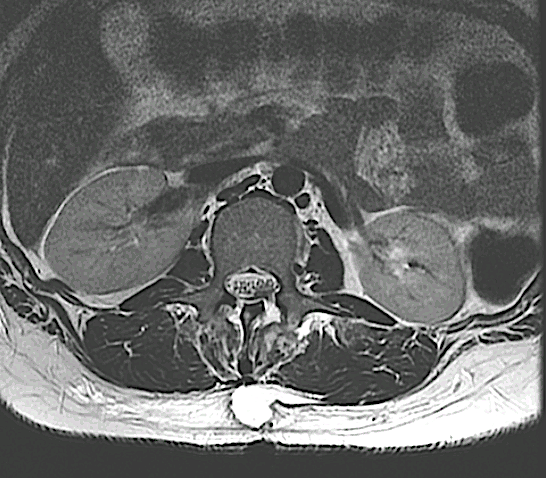

Paciente 73 años con lumbalgia inespecífica asociada a disestesias ocasionales en L3 derecha.

En este caso, a diferencia del caso «Schwannoma lumbar (L3, “raíz no elocuente” ), se optó por un abordaje longitudinal medial con laminotomía + laminoplastia L1 y resección parcial lámina Th12.

Control RM postoperatorio con exéresis completa. Obsérvese el trazo de la laminotomía con la integridad de grupos musculares.